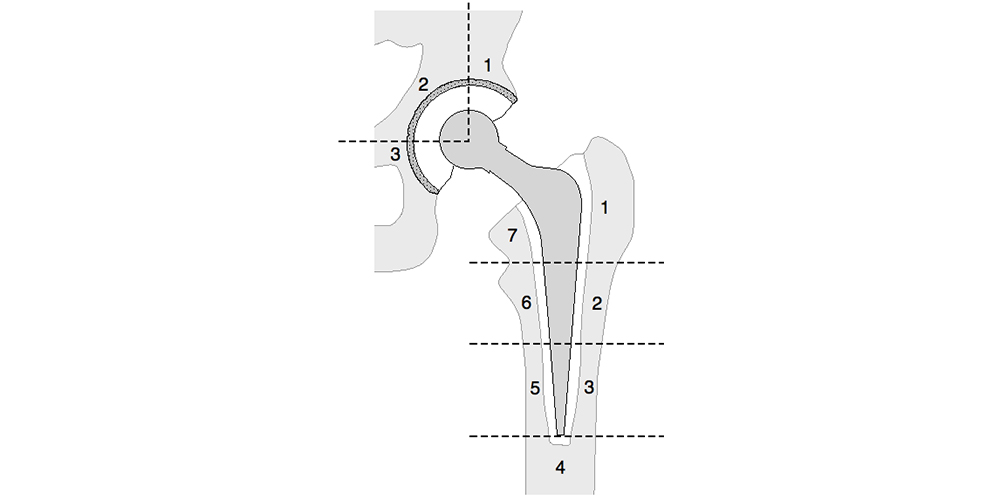

- Afrouxamento asséptico: radiograficamente manifesta-se como uma zona de radioluscência na interface metal-osso ou cimento-osso. As zonas de radioluscência femoral (proposta por Gruen) e acetabular (proposta por De Lee e Charnley) podem ser indentificadas conforme a Figura 17. Normalmente resulta de picos torsionais em retroversão, como para se levantar de uma cadeira ou subir escadas. Forças axiais também podem estar presentes. Uma superfície de metal áspera pode aumentar a força de união entre o implante e o cimento. Entretanto, com a soltura progressiva, o movimento entre as superfícies gera um mecanismo abrasivo que produz inúmeras partículas de metal e de cimento. Com a utilização de implantes de superfície lisa este efeito é menor. Utilizando a técnica de cimentação de primeira geração, com seguimento variando de 15 a 20 anos, a taxa de soltura variou entre 7 e 36% para o componente femoral. Quando se utiliza a técnica de cimentação de segunda geração, as taxas de soltura para um seguimento de 9 a 18 anos variam entre 1,3 a 6%. Em relação ao componente acetabular, as taxas de soltura para um seguimento de 17 a 20 anos podem variar de 15 a 54% dependendo da técnica e do material utilizado (2,7,41).

Fig. 17. Zonas de radioluscência femoral e acetabular